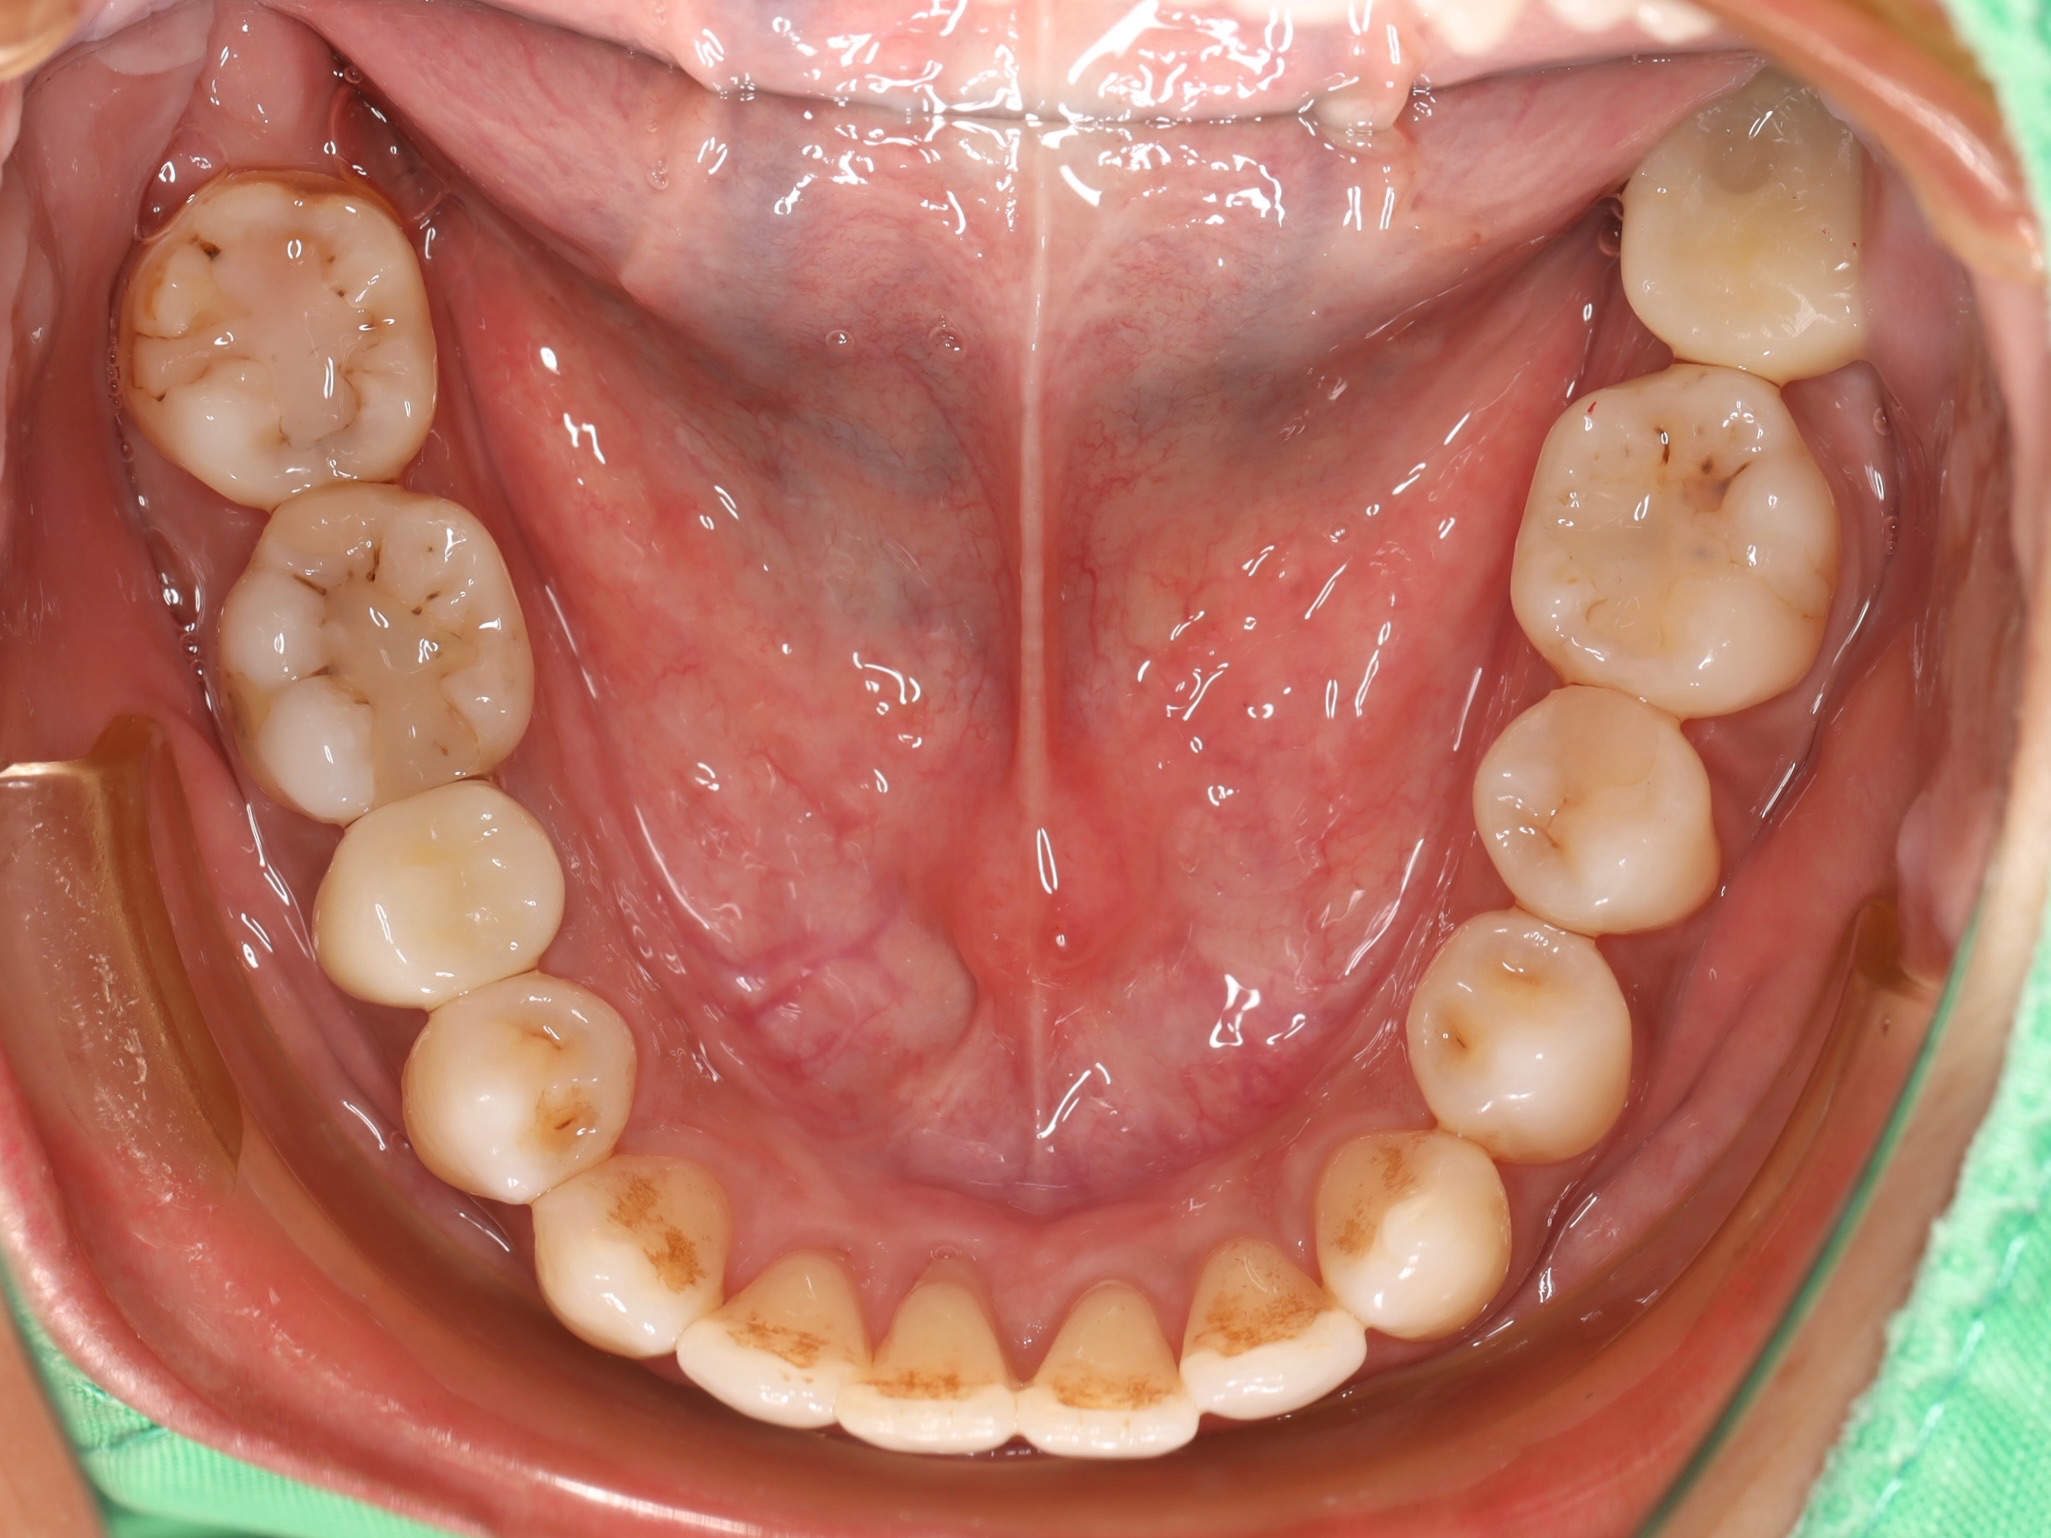

古小姐第一次來到診間時,主要是希望能做全口的詳細評估與檢查,因為她進食較黏稠的食物,牙齒容易感到疼痛,刷牙的時候容易出血,更令她困擾的問題是,她以前因為蛀牙拔掉牙齒,但沒有進行後續處理,左下方有缺牙的情況,除了導致牙齒開始出現縫隙,長期習慣用右邊進食,也讓她兩邊咬合都不太舒服。

經過全口檢查與評估後,我們發現古小姐的口腔問題相當複雜,主要可以歸納為以下幾個項目:

全口牙周病問題 - 導致刷牙時流血的主因

左邊缺牙問題 - 長期缺牙導致排列與咬合問題

咬合與牙縫問題 - 影響整體美觀與功能